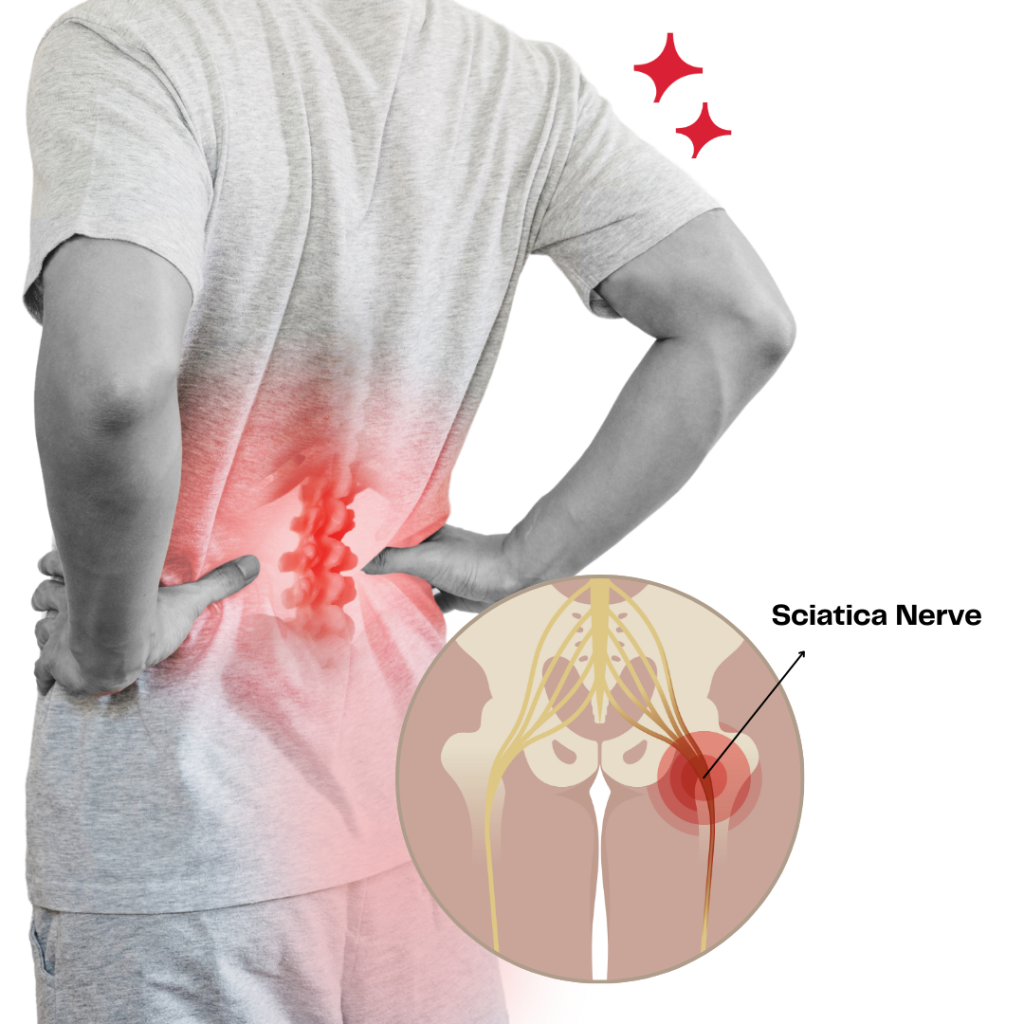

Are You Suffering from Ongoing Pain and Discomfort?

If you identify with any of these symptoms:

- Stiff and achy muscles

- Injuries related to work or exercise

- Neck pain due to prolonged sitting

- Back pain from lifting heavy objects

- Feeling weaker than you'd like to be

We’re here to assist in alleviating your pain and discomfort using proven physiotherapy methods. Many of our patients report noticeable relief after just 3 to 5 sessions. Reach out to us to learn about special offer for new patients.